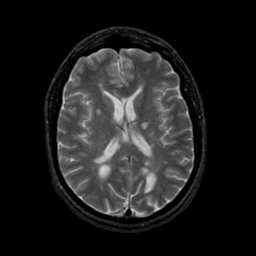

MR Study #23, January 26, 1992 -- Slice #29